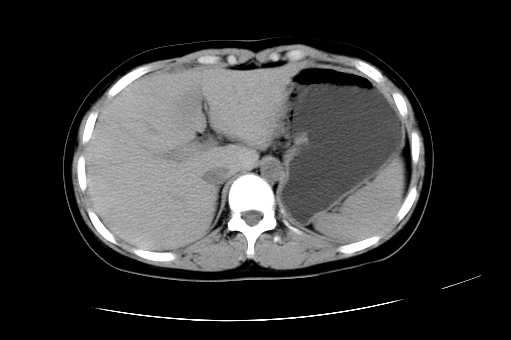

女 16岁  右上腹痛一天,无其他不适

肿块最大径位于十二指肠降段与水平段移行处,并且与肝脏压迹呈“0”形征,可以考虑位于肝外并与胃肠道关系紧密,考虑胃肠道间质瘤(gist)可能较大,须除外神经节起源肿瘤。

肿块与十二指肠关系密切,支持间质瘤诊断.肝脏与结肠均为受压改变.

右下腹巨大肿快,密度不均匀,内见坏死低密度区,边界清楚,与周边胀器明显有分界,未见强化,多考虑来源于间叶组织的良性肿物.

病灶巨大,少部分向肠腔内生长,大部分向长腔外生长。其密度不均匀,增强显示明显不均匀强化,并见有大片状始终不强化的不规则坏死液化区。虽然病灶中上部形态尚可,病人又如此年轻,但中下部形态、密度、强化特点强烈提示为恶性病灶。综上,我考虑本病例为:恶性胃肠道间质瘤。